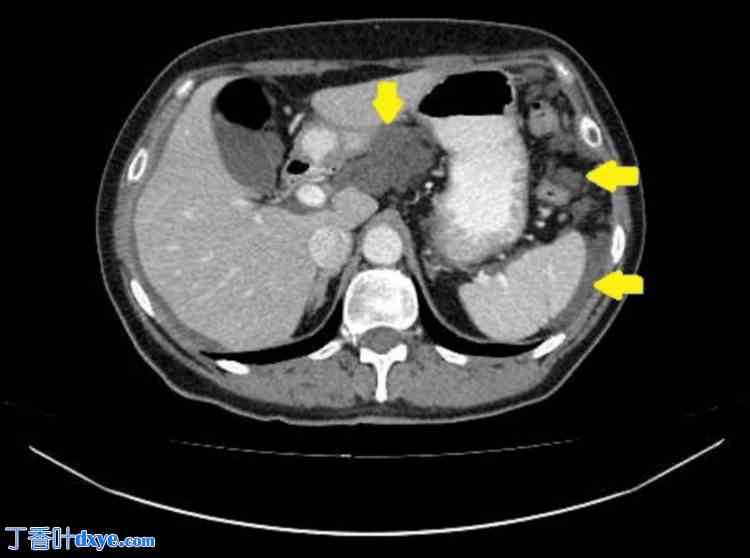

胸部、腹部和盆腔CT扫描(静脉注射造影剂)显示肝周、脾周及盆腔内多处低密度积液(提示为粘蛋白)。在大网膜、小网膜及侧沟内发现聚集性腹膜沉积物,提示腹膜广泛受累。胸部和腹部器官未见其他病理改变。扫描区域淋巴结未肿大。未见骨质破坏或成骨细胞活动征象(图1-4)。

图3. 腹膜转移灶及腹部和盆腔局部积液的CT成像。

箭头所示为大网膜转移灶。